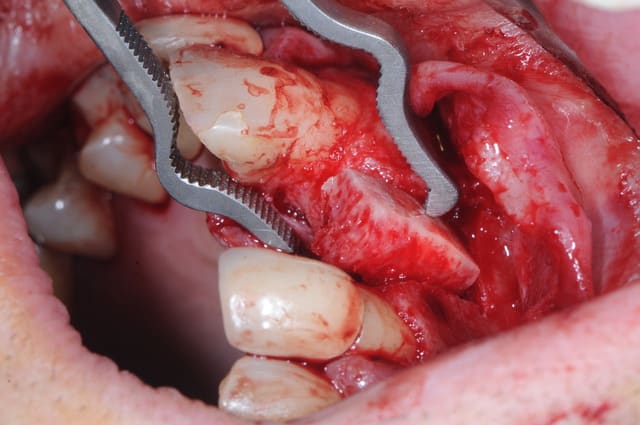

5: bloc de Biobank avec sa partie corticalisée

6-7: perçage du greffon

3 vérification de l'adaptation du greffon au lit receveur

(au moins avec cette technique on a pas beaucoup de travail de préparation...)

4 stabilisation pince stoma

5 greffon en place